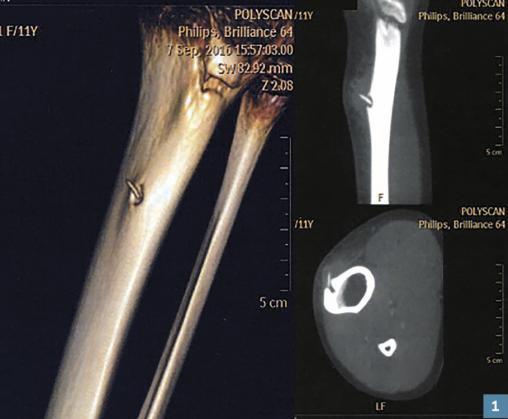

Le scanner injecté avec reconstruction 3D confirme l’ostéite corticale tibiale par pénétration d’un radiole (épine) d’oursin qui s’est planté dans l’os (fig. 1 ). La patiente se souvient s’être cogné le genou gauche contre le fond du lagon en sautant d’un ponton, 3 mois auparavant. La zone est infestée d’oursins diadème (Diadema setosum, fig. 2 ).

À l’échographie : zone hypo-échogène para-osseuse en communication avec une lacune osseuse corticale dans laquelle on voit un élément dense oblique mesurant 9 x 1,5 mm. L’aspect évoquant une ostéite avec collection paratibiale et séquestre osseux, une TDM est demandée.